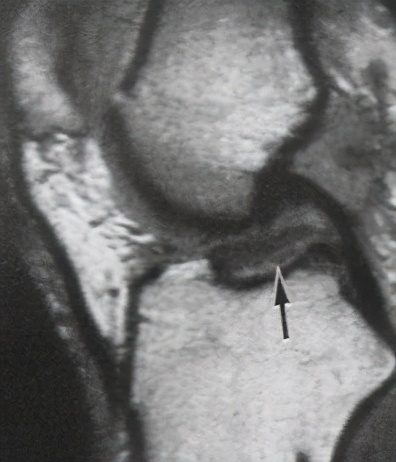

一般膝关节韧带损伤都有外伤病史,以青少年居多,男性多于女性,以运动员最为多见,受伤时有时可听到韧带断裂的响声,很快便因剧烈疼痛而不能再继续运动或工作膝关节处出现肿胀,压痛与积液(血),膝部肌痉挛,患者不敢活动膝部,膝关节处于强迫体位,或伸直,或屈曲膝关节侧副韧带的断裂处有明显的压痛点。高处跌落,车祸等直接*力暴**也可直接至韧带损伤或同时伴有骨折等其他损伤。韧带损伤常常合并膝关节半月板损伤。膝关节MRI检查可以辅助诊断,可以清晰显示出前、后交叉韧带的情况,还可以发现隐匿的骨折线及半月板损伤。下图左边是正常前交叉韧带,右边是损伤前交叉韧带

重建术前的 前交叉韧带 :